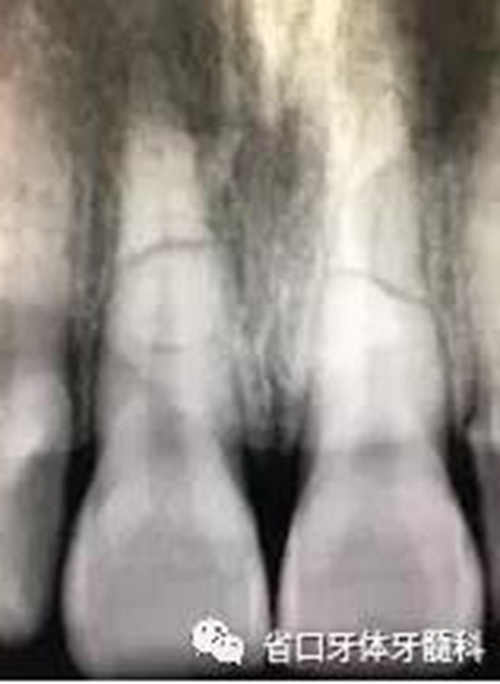

圖1:術前口內(nèi)照

X線片:11、21根中段見橫行根折線,無移位,根尖無明顯異常。